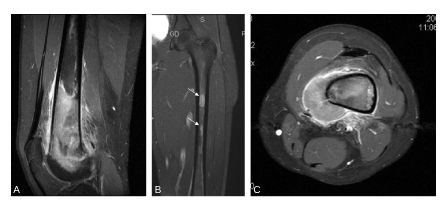

Fig. 120.3 Bilan d’extension locorégional par IRM.

L’IRM confirme la lésion évolutive du tiers inférieur du fémur s’étendant dans la diaphyse et dans l’épiphyse (coupes sagittale A et coronale B en T1 gadolinium saturation de graisse), avec la présence de « skip-métastases » dans la médullaire (B, flèches), et une atteinte des tissus mous (C, coupe axiale T1 gadolinium saturation de graisse).

Source : CERF, CNEBMN, 2022.